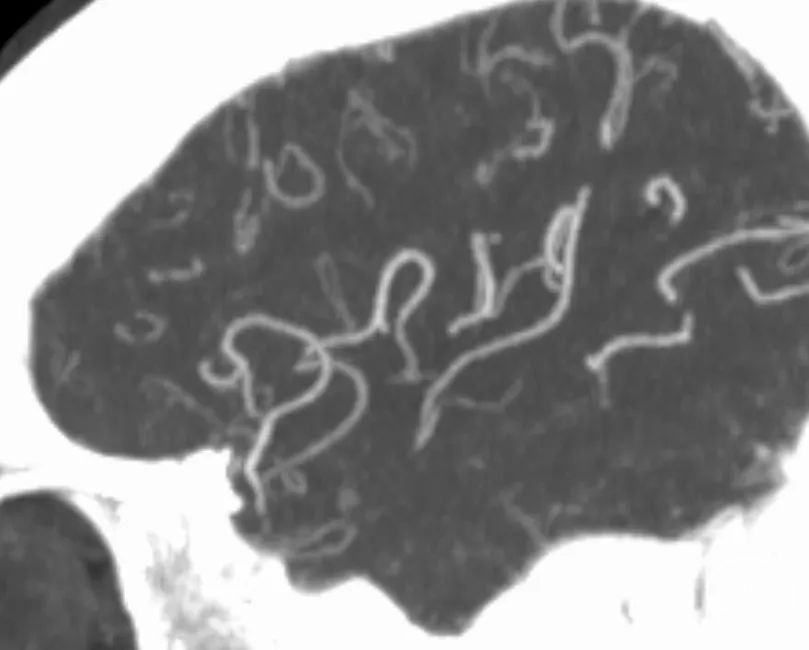

颅脑CT平扫

CTA

CTP

颅脑MRI